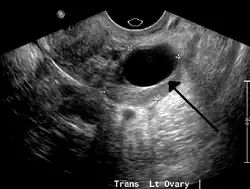

A 2 cm left ovarian cyst as seen on ultrasound

Ovarian cysts are usually diagnosed by pelvic ultrasound, CT scan, or MRI, and correlated with clinical presentation and endocrinologic tests as appropriate.[15] Ultrasound is the most important imaging modality, as abnormalities seen in a CT scan sometimes prove to be normal in ultrasound.[5][8] If a different modality is needed, then MRIs are more reliable than CT scans.[5]

Ultrasound

Usually, an experienced sonographer can readily identify benign ovarian cysts, often with a level of accuracy that rivals other approaches.[5]

Follow-up imaging in women of reproductive age for incidentally discovered simple cysts on ultrasound is not needed until 5 cm, as these are usually normal ovarian follicles. Simple cysts 5 to 7 cm in premenopausal females should be followed yearly. Simple cysts larger than 7 cm require further imaging with MRI or surgical assessment. Because they are large, they cannot be reliably assessed by ultrasound alone; it can be difficult to see posterior wall soft tissue nodularity or thickened septation due to limited ultrasound beam penetrance at this size and depth. For the corpus luteum, a dominant ovulating follicle that typically appears as a cyst with circumferentially thickened walls and crenulated inner margins, follow up is not needed if the cyst is less than 3 cm in diameter.[8] In postmenopausal women, any simple cyst greater than 1 cm but less than 7 cm needs yearly follow-up, while those greater than 7 cm need MRI or surgical evaluation, similar to reproductive age females.[16]